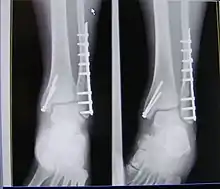

| X-ray of trimalleolar fracture repair before and after ORIF surgery | |

A trimalleolar fracture is a fracture of the ankle that involves the lateral malleolus, the medial malleolus, and the distal posterior aspect of the tibia, which can be termed the posterior malleolus. The trauma is sometimes accompanied by ligament damage and dislocation.[1]

Surgical repair using open reduction and internal fixation is generally required, and because there is no lateral restraint of the foot, the ankle cannot bear any weight while the bone knits. This typically takes six weeks in an otherwise healthy person, but can take as much as twelve weeks. Non-surgical treatment may sometimes be considered in cases where the patient has significant health problems or where the risk of surgery may be too great.[1]